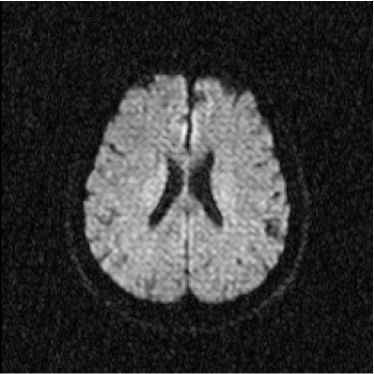

Figure 2: Axial DW-MR image of 13th slice with diffusion exponent of 500 s/mm2

Refer to caption

To perform the training we chose 13th slice of each volume sample (figures 1, 2 and 3), once this slice shows the temporal corni of the lateral ventriculi. The exhibition of such structures facilitates the analysis of the specialist and helps him to find a correlation between data generated by our computational tool and a priori specialist knowledge. Furthermore, slice 13 presents a considerable amount of artifacts out of the cranial region.